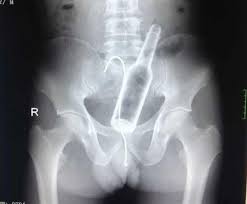

Kazayla Giren Nesneler

O Şişe Oraya Bakın Nasıl Girmiş…Röntgen filmlerinden çıkan akılalmaz şeyler Röntgen filmlerinden “akıl almaz şeyler Hastane koridorlarına düşenler bilir…